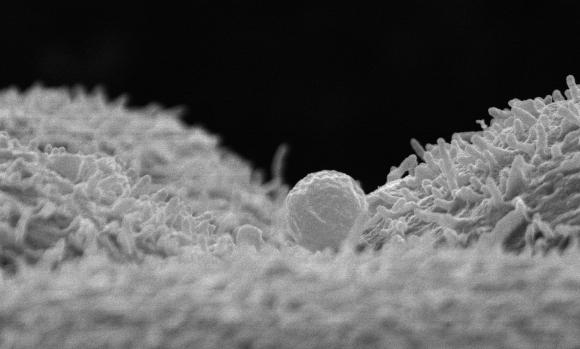

A partir de esta investigación, explicó Fernández Piri, la respuesta es “sí” porque esa futura madre (si bien no le transmitirá su propia carga genética a su bebé) “aportará a la modelación de los genes del bebé”. “Eso, según reveló la investigación, sucede porque las moléculas micro ARN (ácido ribonucleico) que navegan dentro de una especie de ’saquitos’ llamados ’exosomas’ por el líquido endometrial entran en contacto con el núcleo del embrión, que es donde está el ADN”, explicó.

Ese intercambio entre las moléculas de la madre gestante y el ADN (ácido desoxirribonucleico) del embrión -cuyo óvulo provino de otra mujer- va a regular la expresión de algunos genes y otros no, gracias a un mecanismo que se llama epigenética, que es el que permite que del código genético que tiene el embrión, unos genes se expresen y otros no lo hagan”, precisó Fernández Piri, médica y ginecóloga. “Esa es la influencia de la madre gestante: la capacidad de modular la expresión genética de su embrión”, completó la especialista en reproducción asistida. Después de este hallazgo también se sabe que cuando “una mujer se embaraza en su casa -sin pasar por la fertilización asistida- lo que le transmite a su embrión tampoco es sólo su carga genética sino la regulación de ese ADN”. Por esa razón, la madre (aun gestando a su hijo por ovodonación) “seguirá aportando esa capacidad que es la regulación de lo que expresará el ADN del embrión”, afirmó la médica de IVI.